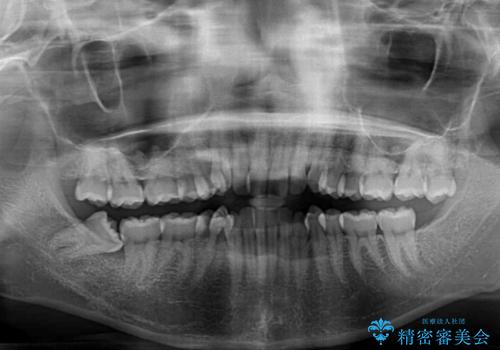

- 前歯のデコボコとクロスバイトを気にして来院された患者様です。

上下ともにデコボコはそれほど強くありませんでしたが、非抜歯では口元が突出した仕上がりとなる可能性があるため、上下左右の第一小臼歯4本を抜歯し、ワイヤー装置での抜歯矯正を行うこととしました